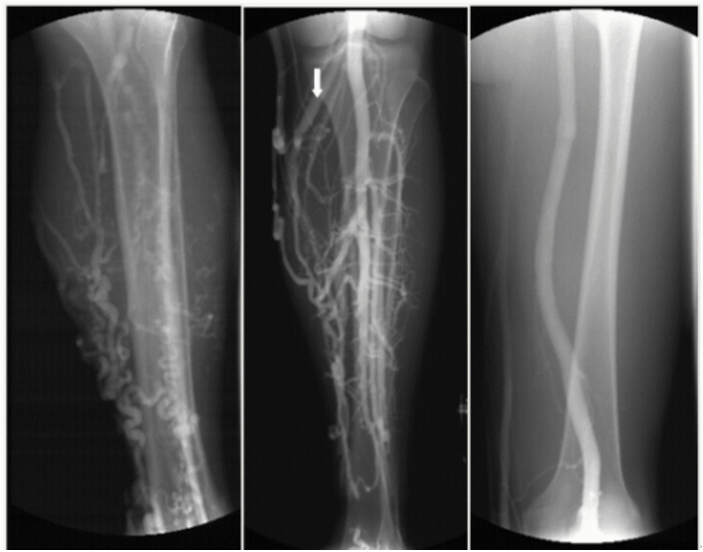

下肢静脉曲张X线造影图像!像蚯蚓一样在患者小腿之上萦绕!

下肢静脉曲张X线造影图像!像蚯蚓一样在患者小腿之上萦绕!